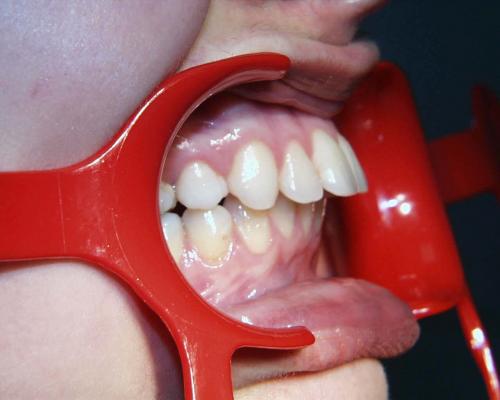

Während der Behandlung

Links Zustand beim Einsetzen der festen Zahnspange, rechts Situation unmittelbar nach der Operation (nach 2 Jahren, 4 Monaten). Der Unterkiefer wurde chirurgisch vorgesetzt und dadurch die Zahnreihen besser in Kontakt gebracht. Die Operation wurde an der Uniklinik Homburg durchgeführt. Eine Feineinstellung der Verzahnung ist aber im Laufe der kieferorthopädischen Nachbehandlung noch erforderlich.